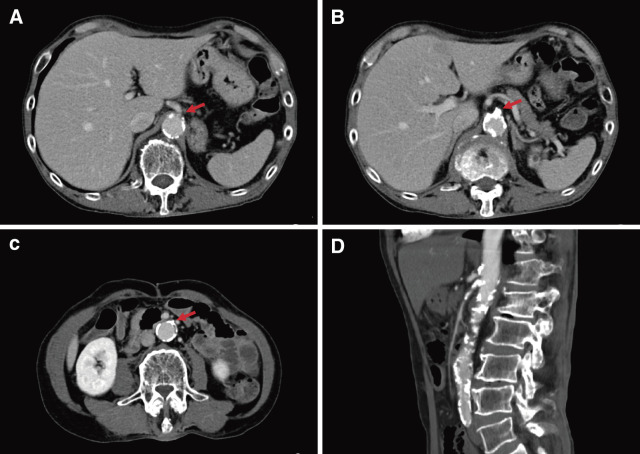

一名 67 岁的男性因餐后腹痛 4 个月而就医。通过 CT 扫描,他被诊断为继发于慢性肠系膜缺血的小肠坏死。我们为他进行了手术,包括小肠部分切除和使用大隐静脉移植左髂外动脉至肠系膜上动脉搭桥术。术后,他的症状有所改善。然而,5 个月后,进食后出现腹痛。CT 扫描发现移植物狭窄,需要进行血管重建手术。重新搭桥手术使用的是人造血管。术后,患者的腹痛症状有所改善。

A 67-year-old male with postprandial abdominal pain for 4 months obtained medical attention for severe pain. He was diagnosed with small intestinal necrosis, secondary to chronic mesenteric ischemia by CT scan. We performed the surgery including a partial resection of the small intestine and left external iliac artery to the superior mesenteric artery bypass using saphenous vein graft. His symptoms improved after surgery. However, 5 months later, abdominal pain appeared after eating. A CT scan identified graft stenosis, leading to a revascularization. A synthetic vessel was used to perform the re-bypass surgery. Postoperatively, the patient's abdominal pain improved.